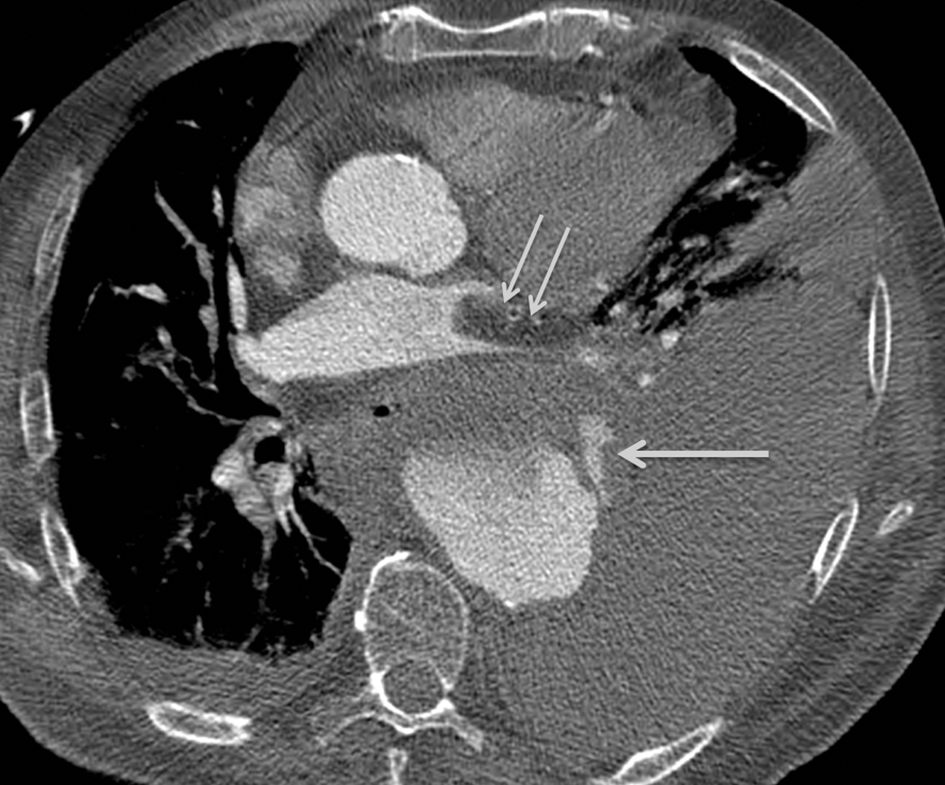

III. Sémiologie

Le diagnostic repose, en scanner abdominal, sur la présence d’un anévrisme de l’aorte abdominale associé à un épanchement hématique péri-aortique (figure 36.4). Parfois, on met en évidence la zone de fissuration avec, très rarement, une extravasation de produit de contraste.

Fig. 36.4. Rupture d’un anévrisme de l’aorte abdominale se traduisant par la présence d’un volumineux hématome rétropéritonéal latéro-aortique gauche (flèches).

Source : CERF, CNEBMN, 2022.